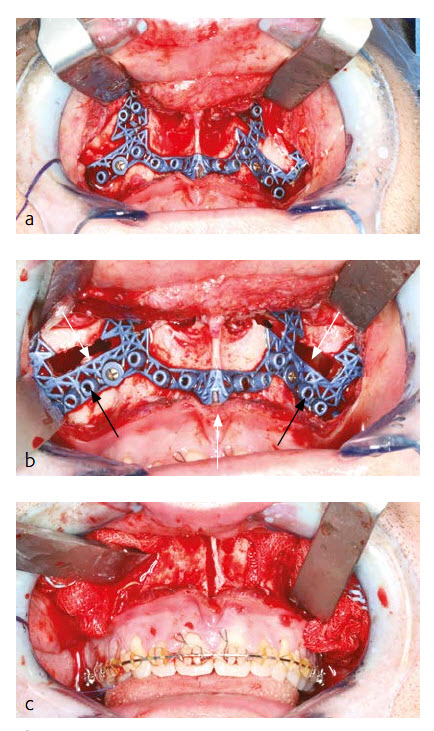

Under general anesthesia via nasal endotracheal intubation, a maxillary vestibular approach was used to gain access for the two-piece Le Fort I osteotomy. Upon maxillary exposure, the surgical guide was placed and fixed with two MatrixMidface 1.5 mm screws on the maxilla (Fig 18a). The position of the guide was determined by the precise fit of the guide which allows a unique position. The screw holes were pre-drilled (black arrow) and Le Fort I osteotomy (white arrow) was performed in accordance to the surgical guide (Fig 18b). After removal of the guide the two-piece Le Fort I osteotomy was completed and the down fracture in combination with the midline split was performed (Fig 18c).

Maxillary positioning in all three dimensions (sagittal, transversal and vertical) was achieved by fixing the patient specific plate in accordance with the pre-drilled screw holes at the maxilla first and at the midface second (Fig 19a). Additional transversal stability of the two-piece Le Fort I osteotomy was achieved by using a transversal wire enforced palatal plate which was manufactured prior to surgery by the dental technician.

The new maxillary position in sagittal, transversal and vertical dimension is encoded in the shape of the patient specific plate. No additional splint (wafer) or intraoperative measurements were necessary for positioning of the maxilla. After closing the maxilla, a classical BSSO with semi rigid SplitFix fixation was performed (Fig 19b) and the final occlusion (Fig 19c) was adjusted using a splint (wafer) in final occlusion.